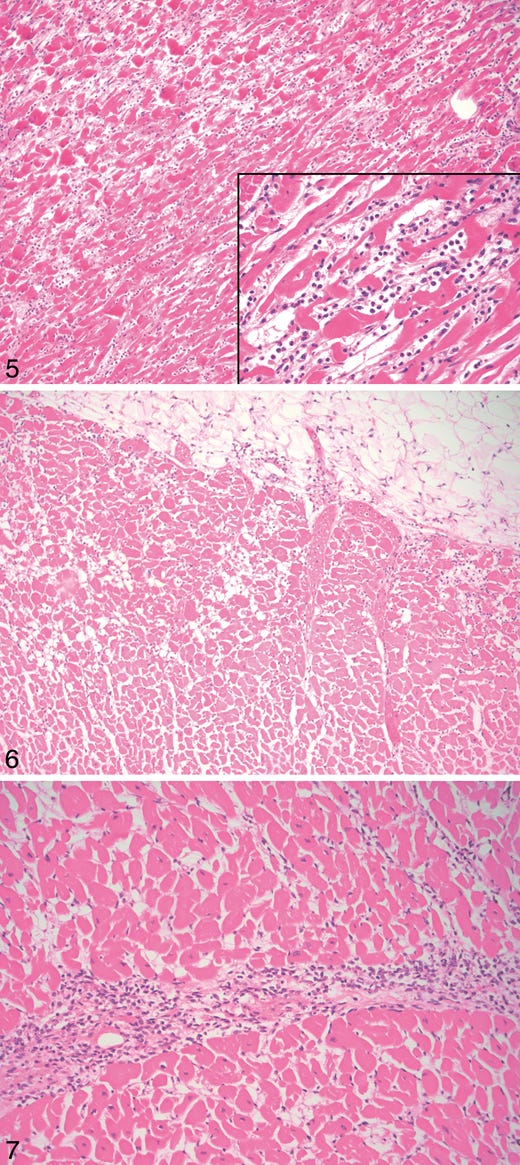

![Case B, heart: hypereosinophilic myocytes, contraction band necrosis, and coagulative myocytolysis. Inset: the infiltrate is predominantly neutrophilic (hematoxylin-eosin, original magnifications ×100 and ×400 [inset]). Case B, heart: hypereosinophilic myocytes, contraction band necrosis, and coagulative myocytolysis. Inset: the infiltrate is predominantly neutrophilic (hematoxylin-eosin, original magnifications ×100 and ×400 [inset]).](https://substackcdn.com/image/fetch/$s_!W9PE!,w_1456,c_limit,f_auto,q_auto:good,fl_progressive:steep/https%3A%2F%2Fsubstack-post-media.s3.amazonaws.com%2Fpublic%2Fimages%2F4cf4b457-5551-45b3-b4e7-7c900fa2c76a_520x1165.png)

Results.—: The microscopic examination revealed features resembling a catecholamine-induced injury, not typical myocarditis pathology.

Conclusions.—: The myocardial injury seen in these postvaccine hearts is different from typical myocarditis and has an appearance most closely resembling a catecholamine-mediated stress (toxic) cardiomyopathy. Understanding that these instances are different from typical myocarditis and that cytokine storm has a known feedback loop with catecholamines may help guide screening and therapy.’